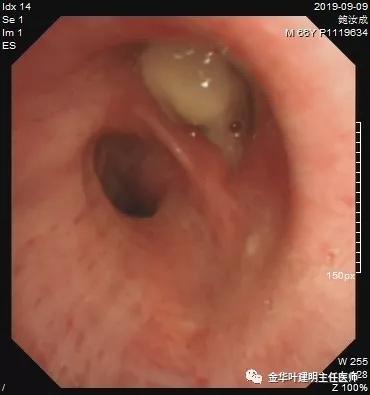

纤支镜所见如下:

病理结果如下:

上图示胸水病理未找到癌细胞

上图示纤支镜病理确诊鳞癌